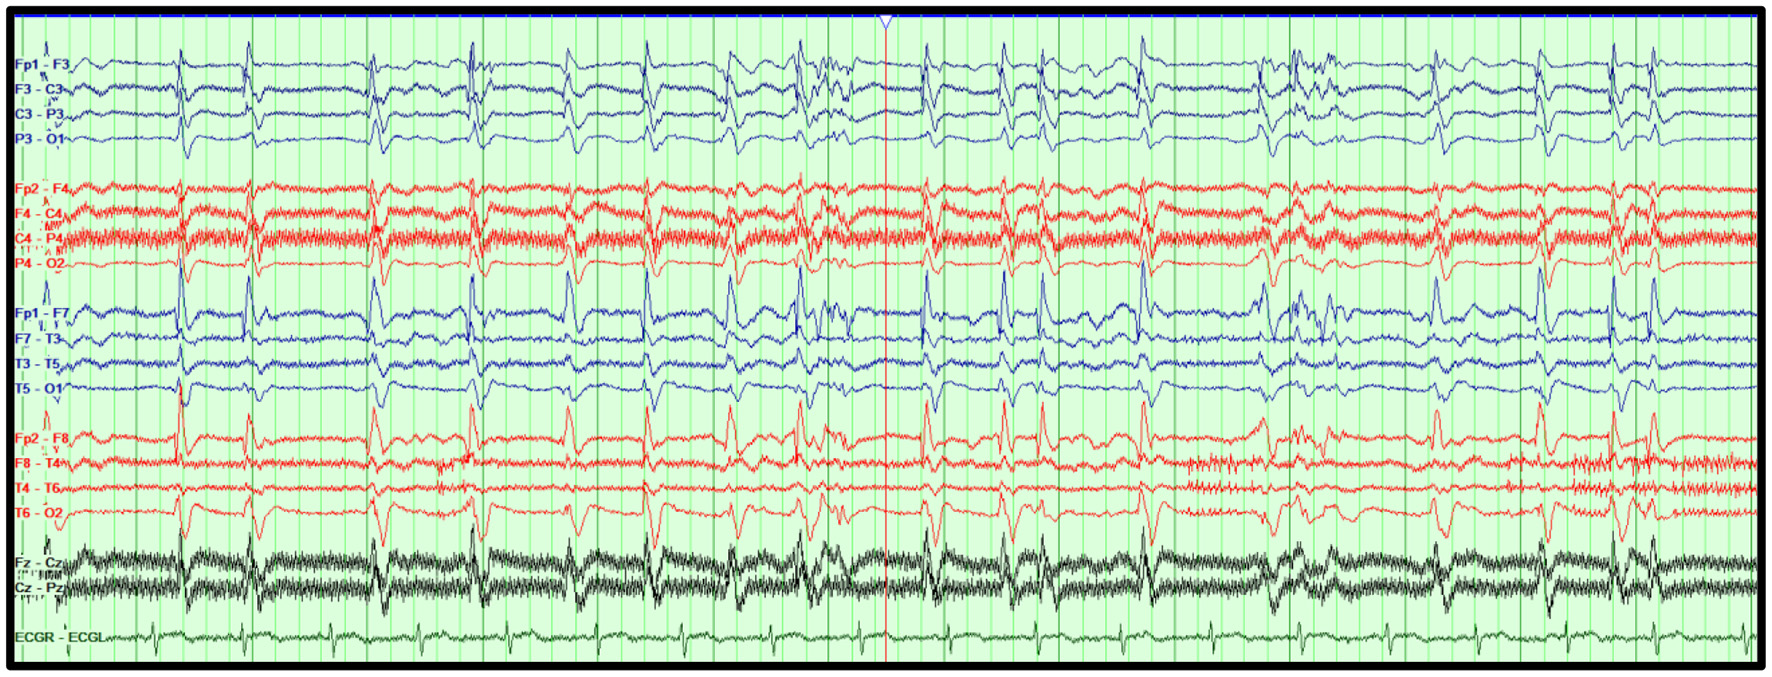

In contrast, electrographic seizures in the absence of a clear clinical change are more challenging to determine. The 2021 ACNS terminology, which is briefly explained below, excludes the unequivocal electrographic seizure definition, which is defined as generalized spike-waves at 3 Hz or more, and/or evolving discharges that reach >4 Hz (5, 46). Figure 3 illustrates an example of an unequivocal electrographic seizure.

Figure 3

Unequivocal electrographic seizure on EEG in the ICU. Right temporal electrographic seizure (A–C) in a 21-year-old woman with herpes simplex (HSV) encephalitis. Average referential montage with double density electrodes added in the bilateral basal temporal regions (T1, F11, T2, F12), LFF: 1 Hz, HFF: 70 Hz, Notch: 60 Hz, Sensitivity: 10 μV/mm, Timebase: 30 mm/s.